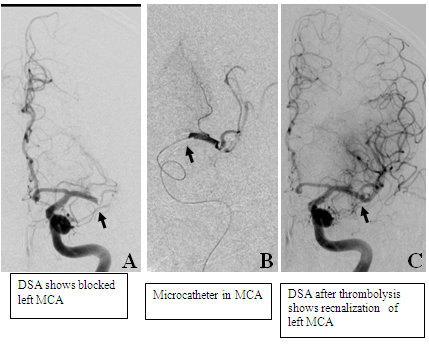

A 64-year-old male presented with suddenonset hemiplegia and aphasia of 4-hours duration. since the time liit for intravenous therapy had already passed, patient was taken up for intra-arterial recnalization. dsa revealed blocked left mca (a). microcthter ws placed in mca and urokinase 95 millio units) was infused resulting in recnalization of mca (c). patient acheived complete clinical recovery.